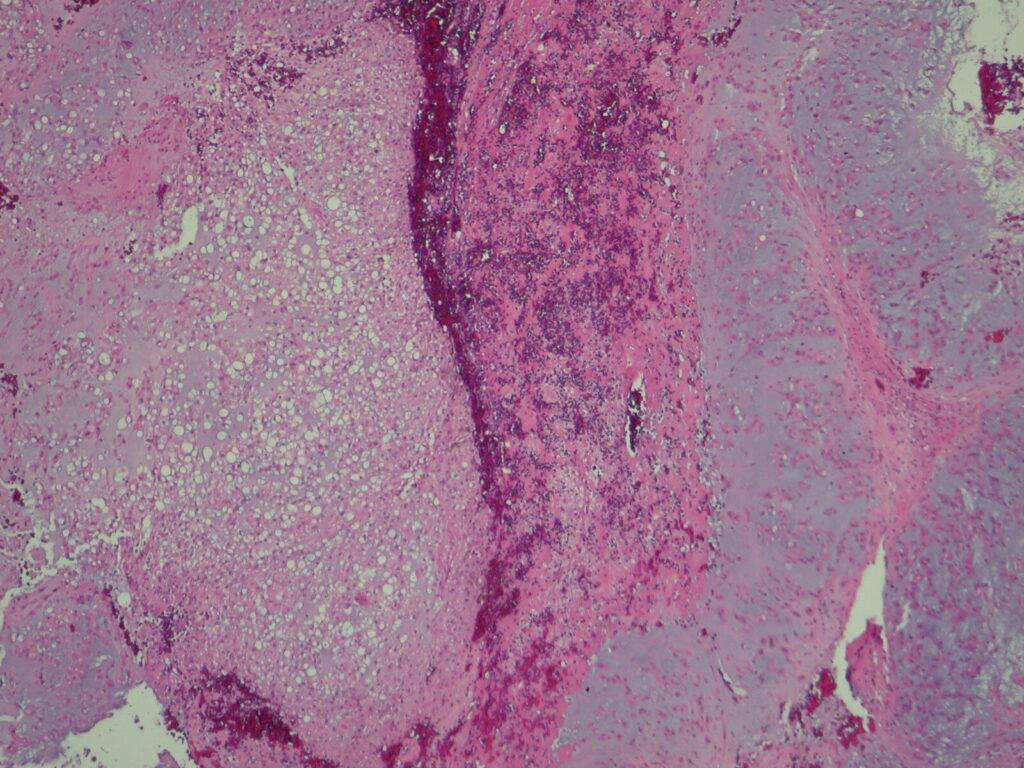

Microscopic (Fig. 13 & 14)

• Proliferation of large cells with eosinophilic cytoplasm with vacuoles (physalipherous cell)

• Nuclei are round/oval with prominent nucleolus

• Physalipherous cells are surrounded by myxoid matrix

• Lobules separated by fibrous septa

• Few nuclear polymorphism

• Few to no mitotic figures

• May exhibit cartilaginous differentiation

Fig. 13 & 14: Microscopic pathology demonstrates hypercelularity forming lobules separated by fibrous septa. Higher magnification shows physaliferous cells that arelarge cells with bubbly cytoplasm surrounded by myxoid matrix. No mitotic figures are distinguished.